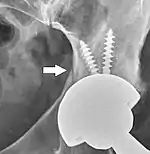

Hip prosthesis displaying aseptic loosening (arrows)

Hip prosthesis zones according to DeLee and Charnley,[29] and Gruen.[30] These are used to describe the location of for example areas of loosening.

On radiography, it is normal to see thin radiolucent areas of less than 2 mm around hip prosthesis components, or between a cement mantle and bone. These may indicate loosening of the prosthesis if they are new or changing, while areas greater than 2 mm may be harmless if they are stable.[31] The most important prognostic factors of cemented cups are absence of radiolucent lines in DeLee and Charnley zone I, as well as adequate cement mantle thickness.[32] In the first year after insertion of uncemented femoral stems, it is normal to have mild subsidence (less than 10 mm).[31] The direct anterior approach has been shown to itself be a risk factor for early femoral component loosening.[33][34][35]